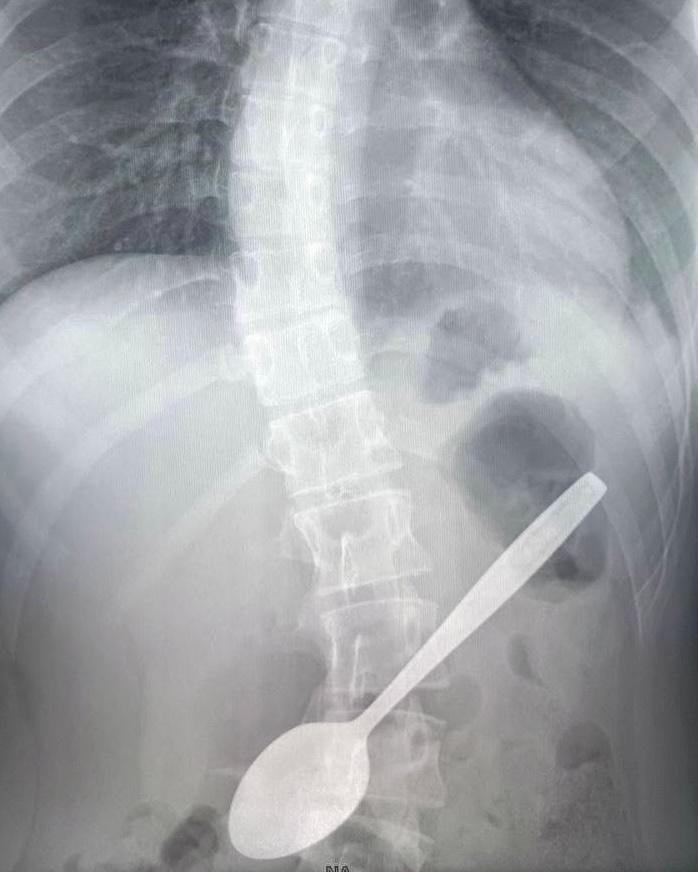

В Подмосковье школьница попыталась вытащить застрявший в горле кусочек яблока чайной ложкой. В итоге ложку она проглотила.

Девочку экстренно доставили в больницу, где врачи успешно извлекли ложку, теперь её состояние стабильное.